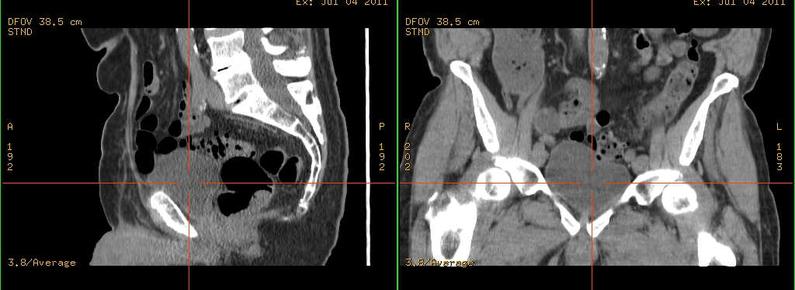

Am #Universitätsklinikum des Saarlandes in #Homburg wurde eine Patientin mit tief infiltrierender #Endometriose erfolgreich behandelt und konnte anschließend ihren